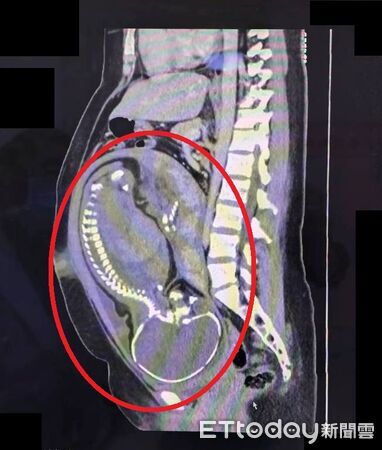

林敬旺說,安排腹部電腦斷層(CT)檢查,並會診一般外科主任劉信誠,經過跨科團隊仔細討論,高度懷疑為急性盲腸炎,且與孕婦及家屬充分溝通解釋後,決定執行緊急剖腹生產併盲腸切除手術。

他表示,手術中發現盲腸已嚴重腫脹化膿,瀕臨破裂邊緣,腹腔內更已有約100毫升的膿樣腹水,情況相當危急。所幸,在妥善保護手術傷口避免污染的情況下,順利接生寶寶,同時完成盲腸切除手術,產婦術後接受抗生素治療,恢復良好、已平安出院。